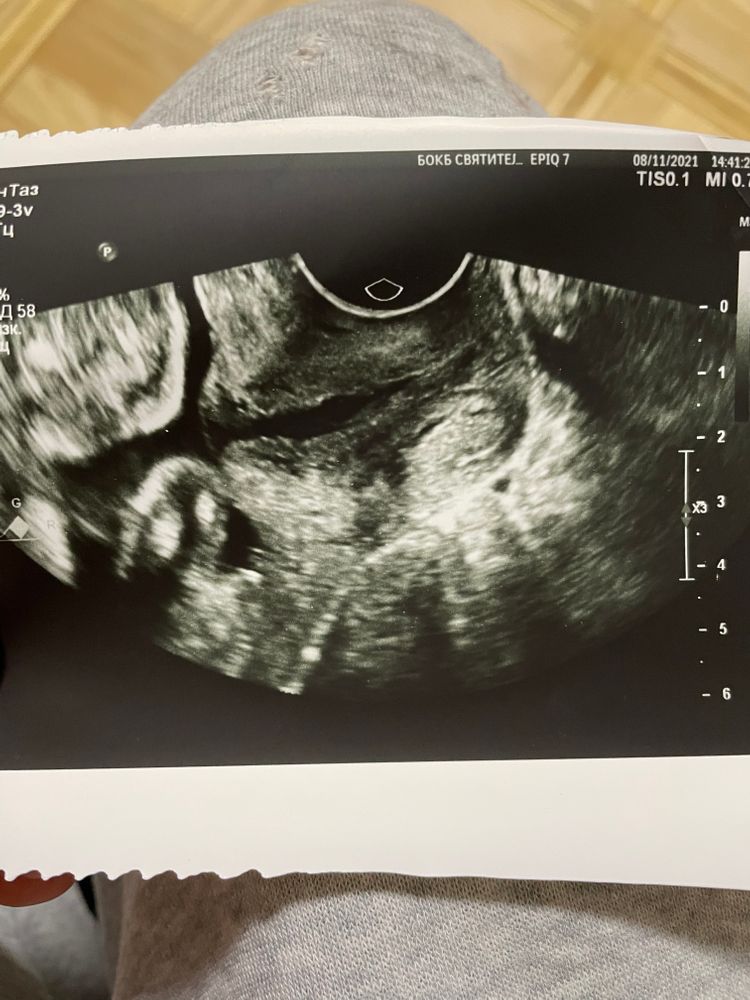

Ромашка, есть🙏🏽Первое фото в 24 недели, второе фото в 28.3 недели в 26 она мне фото не давала

квитка, я, конечно, не врач.. Но цервикометрий в своей жизни сделала штук 40.

Визуально не очень выглядит. Зев все таки больше U, чем T.

По всяким их протоколам после 26 нед диагноз Ицн не правомочен. Но вы молодец, что мониторите. Я думаю, что вы спокойно доносите, тк с 24 нет отрицательной динамики. Но обязательно держите на контроле дальше.

Аня Жеребьёва, а еще он у меня сомкнут, но не по всей длине, ну и с 24 по 28 неделю ничего не ухудшилось насколько я понимаю